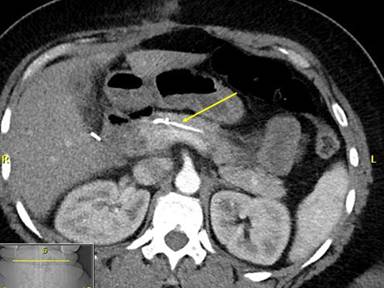

A 43-year-old female with history of morbid obesity (BMI equal to 45 kg/m2), dietary controlled diabetes mellitus, and depression presented to an outside institution complaining of a three-month history of persistent and worsening vague abdominal pain. She was found to have cholelithiasis by ultrasound as well as a dilated bile duct with abnormal liver enzymes. She underwent ERCP with failure to cannulate the bile duct. After several pancreatograms, a 3 cm long 5 Fr single pigtail pancreatic stent was placed to prevent post ERCP pancreatitis. The pancreatic duct stent was later found to have migrated into the neck of the pancreas, and she subsequently developed moderate pancreatitis after the procedure, requiring a nine day hospitalization. Two subsequent endoscopic attempts to remove the impacted stent were performed on days 5 and 26 after the first ERCP, but these were unsuccessful. The patient continued to have epigastric pain with amylase elevation and was also found to have radiographic evidence of acute cholecystitis. She underwent a reportedly difficult laparoscopic cholecystectomy, which was associated with a prolonged recovery time. The patient was then referred to our institution. A fourth attempt of endoscopic extraction was attempted but unsuccessful due to the inability to pass a guidewire past the embedded stent. This last ERCP revealed a proximally migrated stent into the ventral pancreatic duct at the level of the genu and proximal body of the pancreas (Figure 1). The main duct and side branches were moderately dilated. A computerized tomography scan showed the stent causing proximal pancreatic ductal dilation (Figure 2). The patient was then consulted for surgical management of the impacted stent.

Figure 2. Computerized axial tomographic image showing the impacted retained pancreatic duct stent (arrow). |